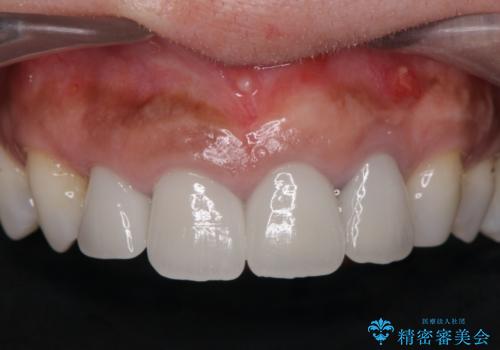

- 前歯がグラグラし、においもする、とのことで改善を求めて来院されました。

一見して問題ないように見える左側の2前歯は、セラミックを除去してみると亀裂や虫歯の再発が見られました。

抜歯時に可及的に歯肉のボリュームを保つよう骨充填材とコラーゲン製剤による填塞を行い審美的かつ機能的なブリッジとなるよう治療を進めます。